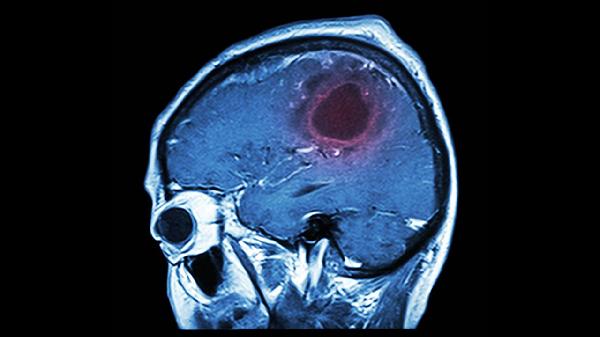

不同身体部位CT扫描的辐射剂量差异显著。头颅CT单次有效剂量约2毫西弗,而腹部盆腔联合扫描可达10-20毫西弗。高剂量区域重复检查需更谨慎评估必要性。